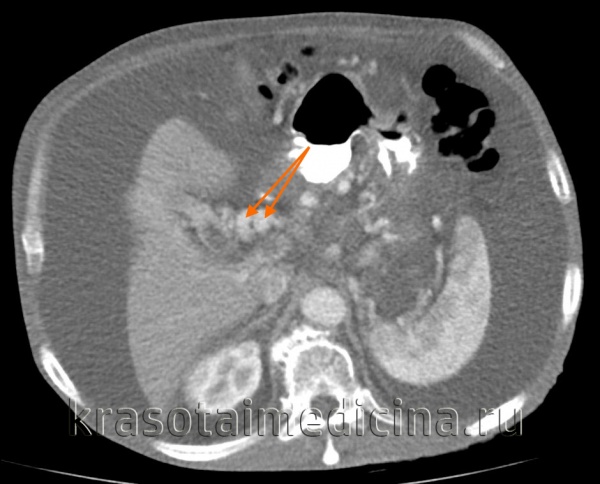

КТ ОБП. Портальная гипертензия на фоне обструкции воротной вены опухолью поджелудочной железы (красная стрелка). Опухолевый тромб (зеленая стрелка) в воротной вене. Асцит (белая стрелка).

КТ ОБП. Этот же пациент, расширенный левый долевой ствол воротной вены (синяя стрелка) с периваскулярным отеком (желтая стрелка).

КТ ОБП. Этот же пациент, варикозно расширенные вены как проявление синдрома портальной гипертензии (коричневая стрелка).